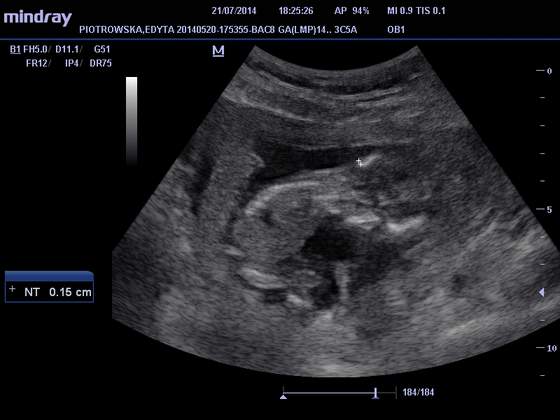

A oto moje dziecie :)

Ma 8.36 cm, rośnie jak na drożdżach :D

Odpowiada 14w2d :)